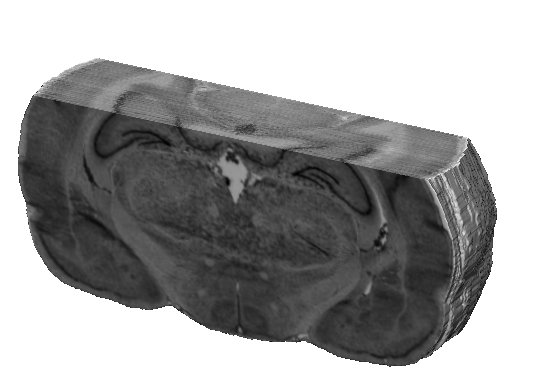

BrainRAT toolbox | BioPICSEL, MIRCEN, CEA | 3.1 or > | all | Ex vivo 3D reconstruction and analysis |